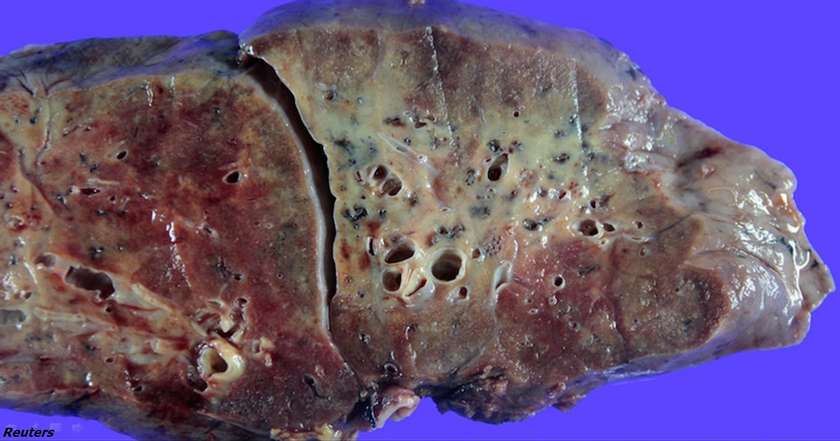

Հյուսիսային Կորեայի բժիշկները ցույց են տվել թե ինչպիսի տեսք ունի COVID-19-ով վարակված հիվանդի թոքերը: Սա իսկապես սարսափելի է:

Արդյունքում սկսում է բորբոքումը, թոքերը ջրով են լցվում և չեն կարողանում իրենց ֆունկցիան կատարել: Համակարգչային տոմոգրաֆիայի պատկերների վրա երևում է թե ինչ տեսք ունեն թոքերը: Որքան շատ են սպիըակ ծակոտիները, այնքան ավելի շատ են թոքերը վնասվում, և մարդն ավելի քիչ հնարավորություն ունի ինքնուրույն շնչելու համար:

Հաջորդ փուլի թոքերի վնասումը կոչվում է «սալաքարային էֆեկտ»: Նկարներում օրինակը ավելի հստակ տեսանելի է դառնում:

Սրանից հետո որպես կանոն, առաջացած սպիտակ ծակոտիները դառնում են լրիվ սպիտակ: Սա ինքնին այդքան էլ վատ չէ, բայց երբ դա ավելի է շատանում, այդ ժամանակ արդեն պետք է անհանգստանալ: